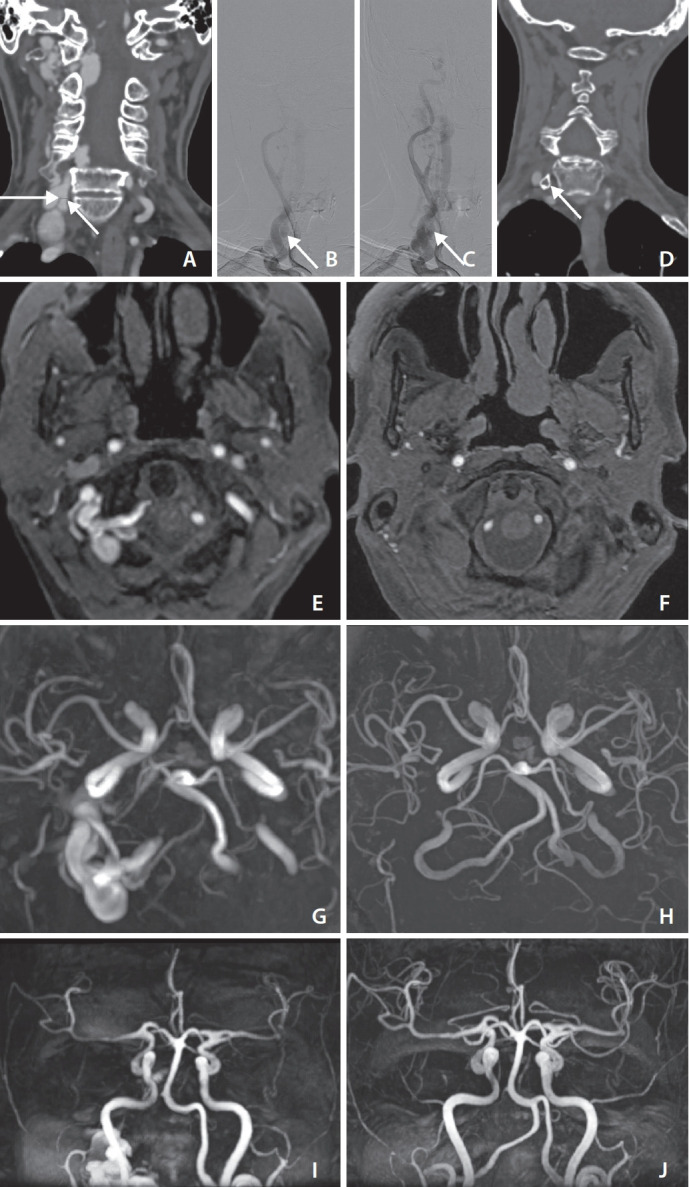

Intrasaccular Flow Disruptor (Woven EndoBridge) Assisted Embolization of Vertebral Arteriovenous Fistulas.